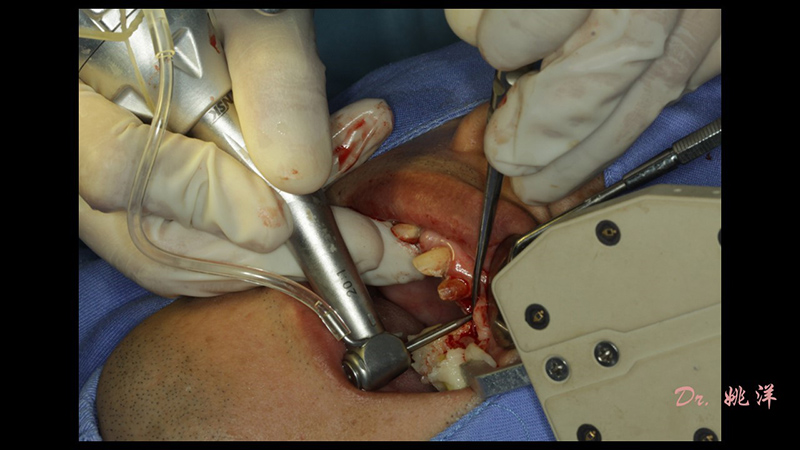

術(shù)中操作

導(dǎo)航下精細(xì)分配修復(fù)間隙,精細(xì)規(guī)劃植入方向,避開(kāi)上頜竇底,精確植入

從術(shù)后CBCT顯示可以看出,手術(shù)操作中完美地避開(kāi)上頜竇底,并兼顧了正確的種植方向和修復(fù)間隙